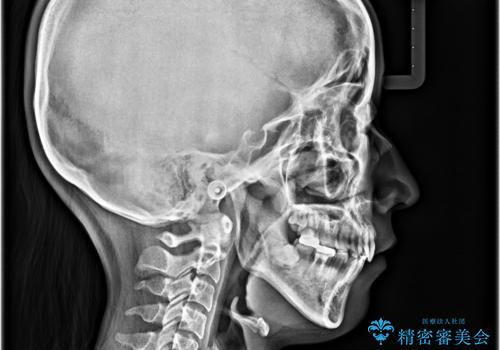

- 前歯のデコボコと口元の突出感を気にして来院された患者様です。

上下前歯がくちばしのように突出していたため、上下左右の第一小臼歯4本を抜歯し、ワイヤー装置にて矯正治療を行うこととしました。

口元の突出感が改善されてことで、下唇に引っかかっていた上顎前歯も気にならなくなりました。